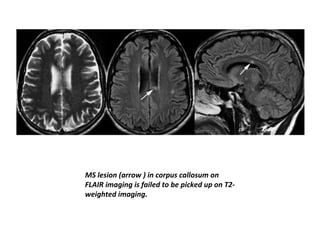

MS lesion (arrow ) in corpus callosum on

FLAIR imaging is failed to be picked up on T2-

weighted imaging.

MS lesion (arrow) in corpus callosum on FLAIR imaging is failed to be picked up on T2- weighted imaging.

• Plaques locatedin the immediate periventricular region may be difficult to appreciate on T2-weighted images (where CSF shows high intensity), and proton density– weighted images or fluid-attenuated inversion recovery (FLAIR) images usually better define periventricular lesions.

• Owing tothe increased tissue contrast in FLAIR, it has improved detection of cerebral hemispheric lesions, especially increased sensitivity to the detection of juxtacortical lesions . • The improved tissue contrast of FLAIR images makes it overall easier to spot lesions at the first glance, probably one of the reasons why this sequence is often preferred over standard T2 weighted sequences.